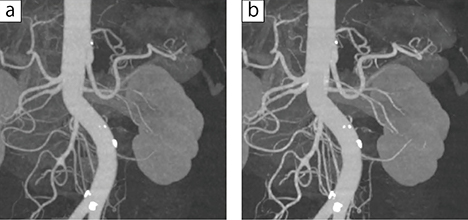

図2 術前造影3D画像

a:AIDR 3D b:AiCE-i

AiCE-iを用いることで、ノイズに埋もれていた末梢血管の描出能が向上した。外科から術前の3DやMIPでの血管構築を求められた際、より精細な画像を提供することが可能になった。